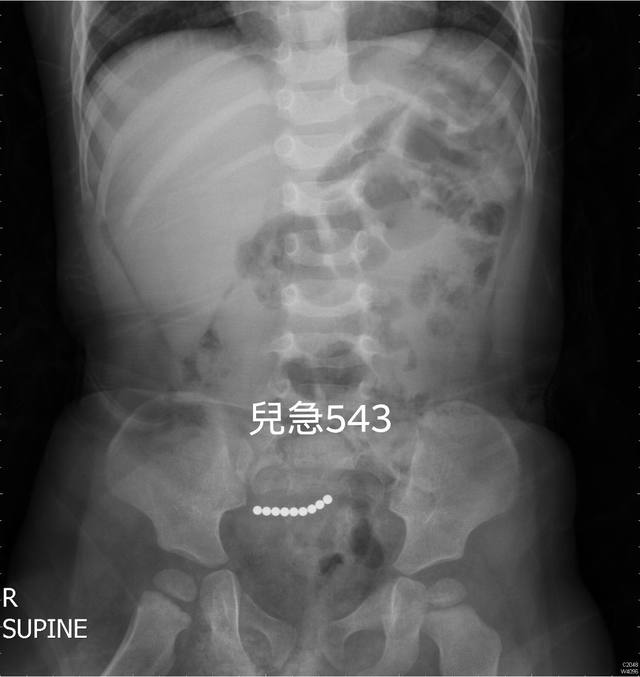

到了兒科急診室後,醫師發現男童有腹脹和輕微上腹痛的情況,於是安排腹部X光片檢查,結果就看到男童腹部有高達9顆「巴克球」,卡進他的小腸腸道,儘管緊急手術取出,但還是造成男童腸道穿孔破裂。